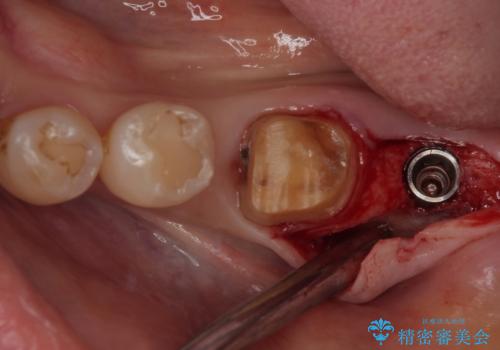

- 口を開けたときに目立ってしまう銀歯をセラミックに替えたいとのことで来院された患者様です。

上顎や親知らずにも銀歯がありましたが、今回の治療では目立つ下顎の銀歯4歯をセラミッククラウンやセラミックインレーに置き換えることにしました。